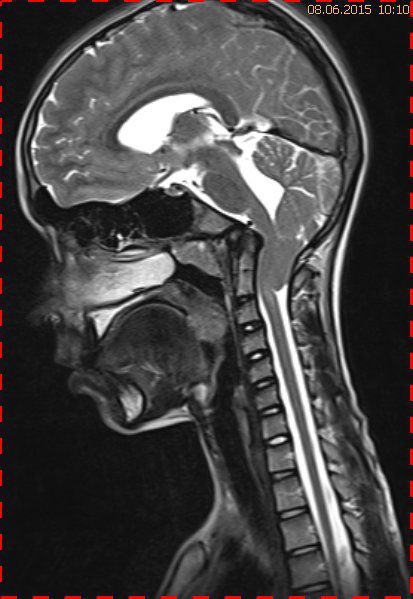

Abb. 1.2 Sagittales MRT (T2 TSE, 1 T): Streckfehlhaltung der HWS und oberen BWS, kein Frakturhinweis oder posttraumatische Myelopathie; die Kleinhirntonsillen reichen bis in das Foramen magnum

Das Fallbeispiel 1 zeigt im Verlauf eine Komplikation bei einer Arnold-Chiari-Malformation Typ 1 bei einem zum Zeitpunkt der Erstdiagnose 12-jährigen Jungen. Dieser hatte im Sportunterricht einen schweren Medizinball geköpft und ein Stauchungs-trauma der Halswirbelsäule erlitten. Nach anfänglich symptomatischer frustraner Therapie wurde er vom behandelnden Orthopäden zur MRT der HWS überwiesen. Es wurde eine Streckfehlhaltung und flachbogig rechtskonvexe Skoliose diagnostiziert, klinisch bestand ein Torticollis. Eine knöcherne oder ligamentäre Verletzung wie auch eine Schädigung des Rückenmarks bzw. eine intraspinale Bandscheibendislokation konnten bildmorphologisch ausgeschlossen werden.

Trotz weiterer Schmerz- und Physiotherapie konnte keine Beschwerdereduktion erreicht werden. 2 Monate später erfolgte eine MRT des Kopfes zum Ausschluss einer posttraumatischen Veränderung.

Bei dieser Untersuchung wurde übersehen, dass die Kleinhirntonsillen in das Foramen magnum disloziert waren und eine Arnold-Chiari-Malformation mit Erweiterung des 4. Ventrikels und des Aquäduktes inklusive Kleinhirntonsillentiefstand vorlag. Bei zwischenzeitlich auswärtig erfolgtem CT der HWS wurde eine Anlagestörung im kraniozervikalen Übergang beschrieben. Eine Kontrolluntersuchung des Kopfes weitere 4 Monate später dokumentierte neben einem medullären Ödem einen progredienten Tonsillentiefstand, der zur neurochirurgischen Behandlung mit operativer Erweiterung des Foramen magnum führte.